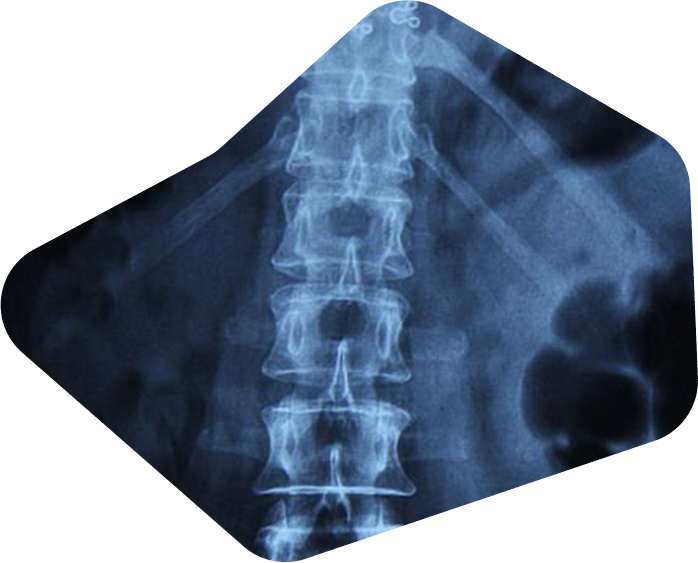

See the spine as it truly moves.

A precise view of the spine in motion.

Spine imaging has relied heavily on static views such as X-ray and MRI. These studies show structure well, yet they limit how motion, instability, and subtle ligament injury appear. TruePath Imaging adds a different layer with Vertebral Motion Analysis, a dynamic study designed to measure spinal motion with precision. VMA reveals abnormal movement patterns that static images overlook, providing objective data early in evaluation and documentation.